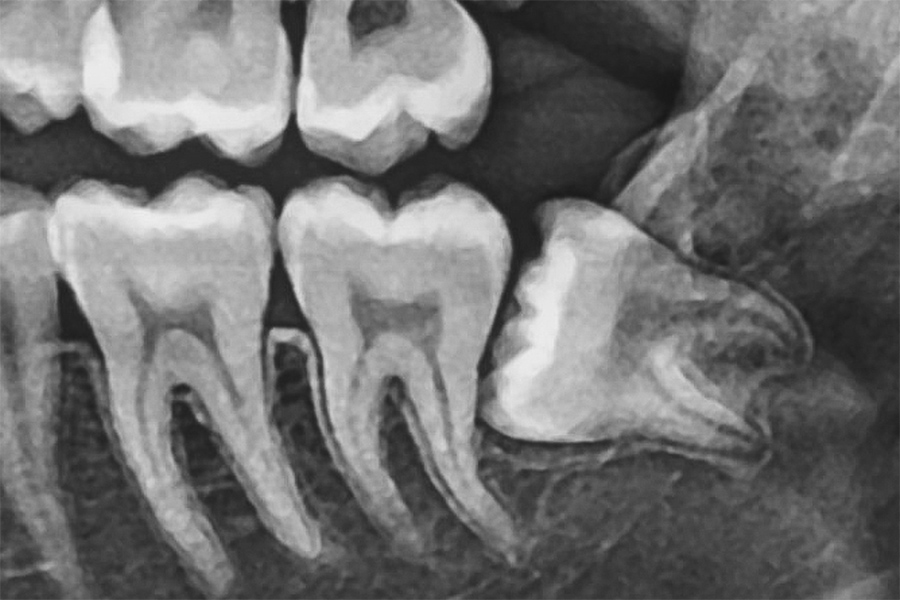

水平埋伏歯にも対応可能です

横向きに生えている「水平埋伏歯」は、手前の歯を圧迫し、痛みや歯並びの乱れ、虫歯・歯周病の原因となることがあります。

さらに、骨や神経に近接しているケースが多く、抜歯には高い専門性が求められます。当院では、精密な診断と高度な技術により、難易度の高い抜歯にも対応しています。

他院で対応が難しいと言われた場合でも、まずはご相談ください。